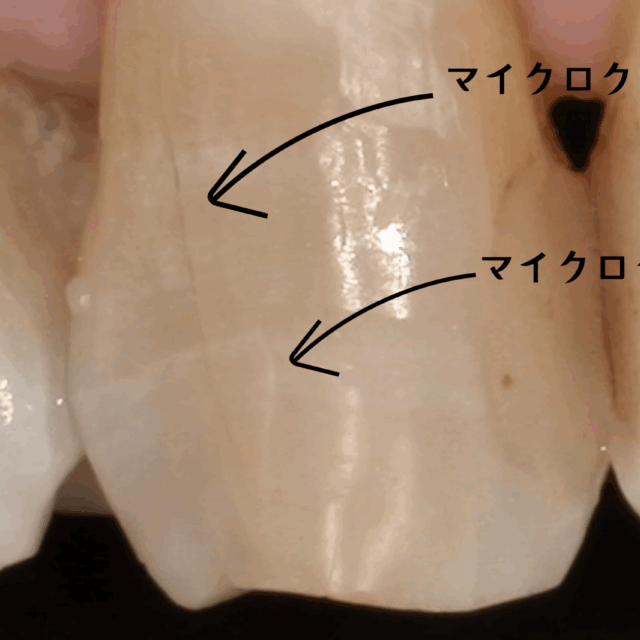

2. マイクロスコープ(歯科用顕微鏡)による精密治療

当院では、院長である私が全てのむし歯治療においてマイクロスコープ(歯科用顕微鏡)を使用します。肉眼の約20倍まで視野を拡大することで、むし歯に感染した部分と健康な歯の境目をミクロン単位で正確に見極めます。

これにより、むし歯の「取り残し」を徹底的に防ぐと同時に、健康な歯を不必要に削りすぎることもありません。